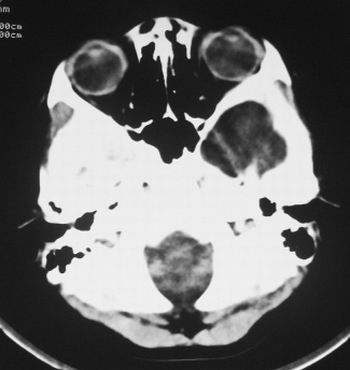

患儿,男,8岁,外伤2小时,无恶心、呕吐,四肢活动正常。既往无任何不适,智力发育正常。

皮样囊肿、蛛网膜囊肿

蛛网膜囊肿,需与表皮样囊肿鉴别。

典型的左中颅窝蛛网膜囊肿。最常见的发病部位,张力比较高,相应颅板受压变薄。赶紧治疗,脑组织的功能可能部分恢复。